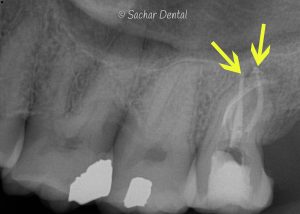

Every tooth has a nerve deep inside of it. When this nerve becomes infected, a root canal procedure becomes necessary. It is important to treat infected nerves. They can be very painful and can cause spreading of infection locally to the bone as well as systemically through the blood and eventually other body parts. It is also worth noting, that sometimes, infected nerves may have no pain at all. It is still important to treat these to prevent the spread of infection.

There are a few reasons why the nerve within a tooth can become infected:

- A cavity that grows large enough or deep enough to touch the nerve within a tooth.

- Large old filings that begin to leak and form a cavity under them.

- Old crowns that begin to leak and form a cavity under them.

- Old root canal procedures can become re-infected.